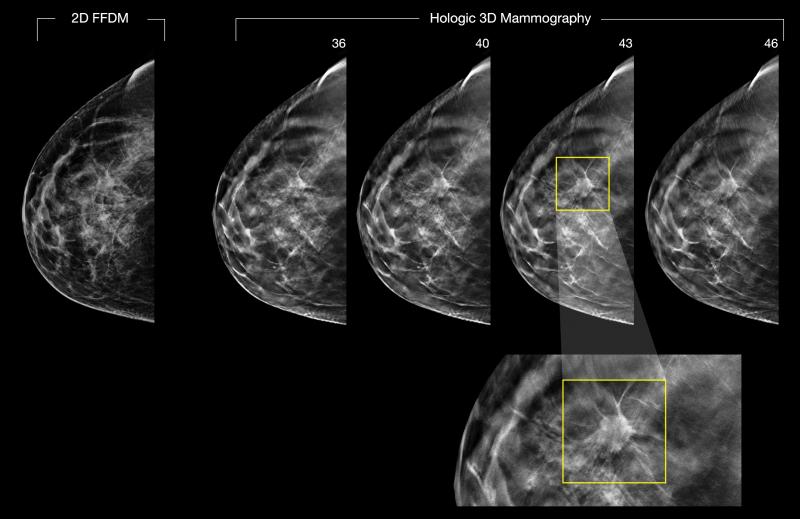

March 11, 2020 — A new study published in the journal Radiology has found that the advantages of digital breast ...